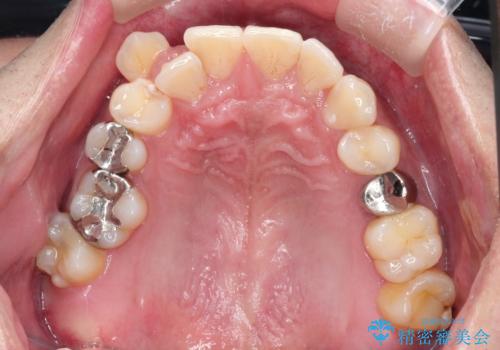

【ワイヤー矯正】八重歯と下の歯の凸凹を治したい

- 主訴:右上の八重歯と、下の歯の凸凹を治したい

上顎右側第一小臼歯と下顎右側第一小臼歯を抜歯しワイヤー矯正を行いました。

右側2級、左側1関係だったため、右側上下第一小臼歯を抜歯し、ワイヤー矯正を行いました。